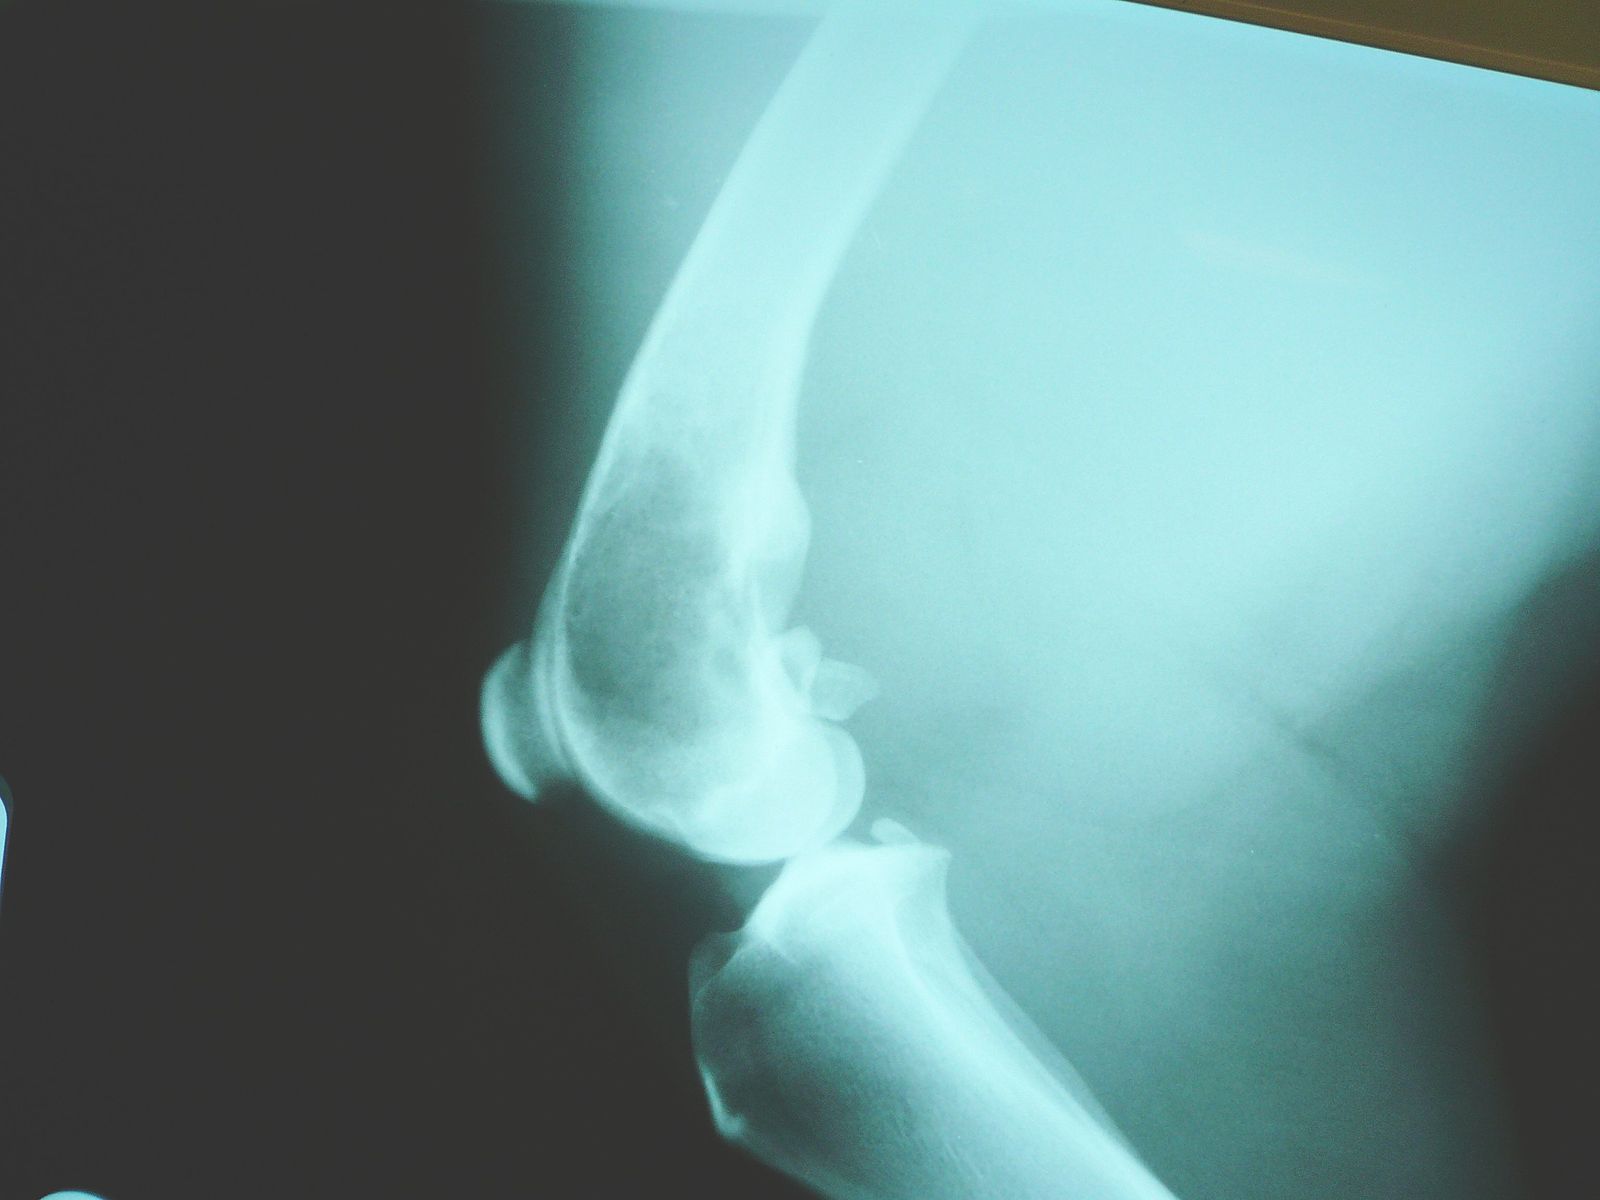

Unfortunately, osteosarcoma is a very common bone cancer found in dogs. It appears as a solid swelling in the affected area, such as the limb or skull, which can spread aggressively to any other part of the body. The tumour may destroy the bone via a pathological fracture, which is when a bone breaks due to disease rather than injury.